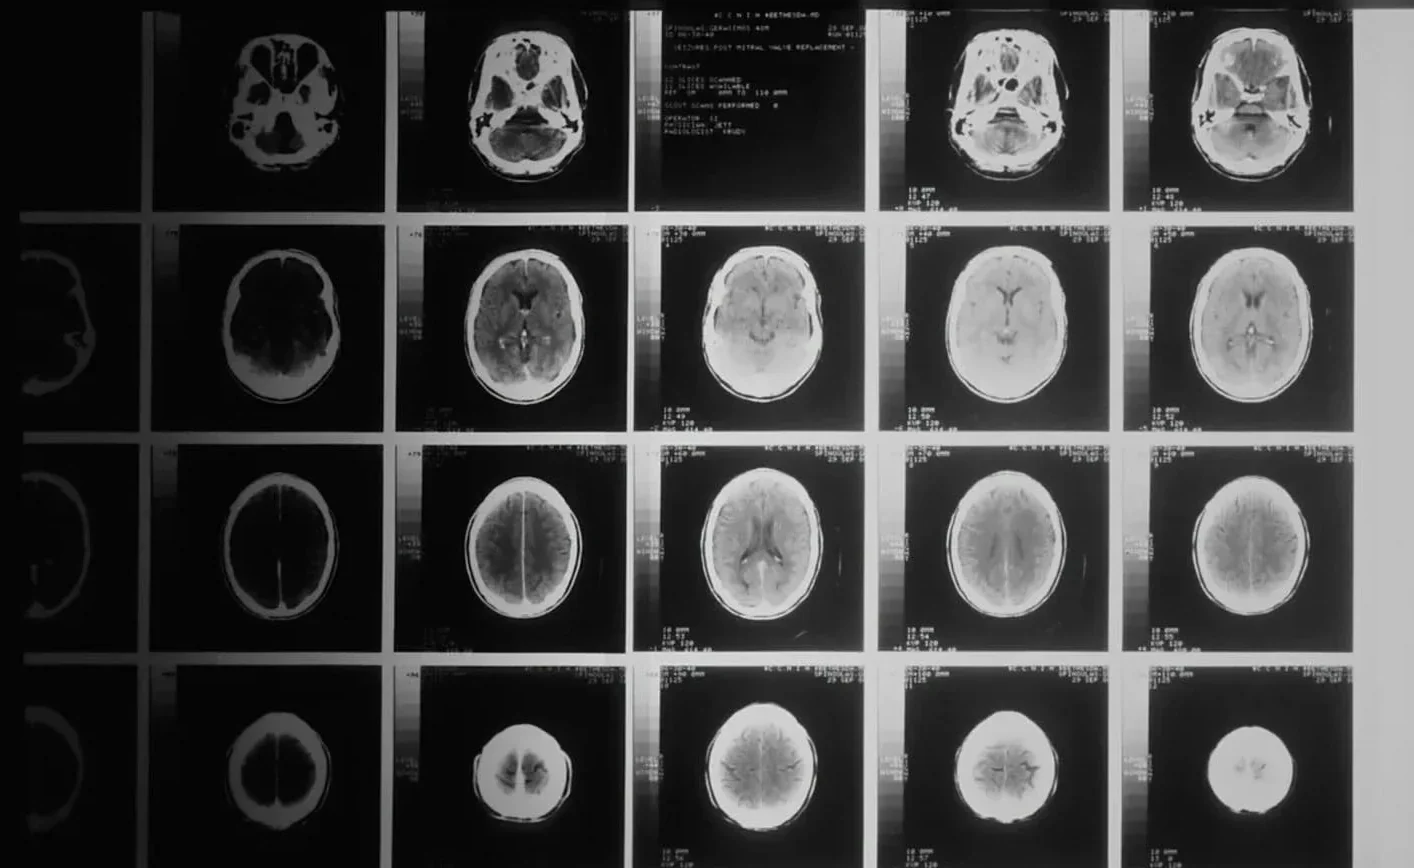

El DIPG se localiza en la base del cerebro y afecta funciones vitales como la respiración y el equilibrio. Representa una de las formas más letales de cáncer pediátrico, con una tasa de mortalidad del 98 % en los primeros cinco años. Por ello, el caso de Lucas supone un hito científico y una nueva esperanza para las familias afectadas por esta enfermedad.